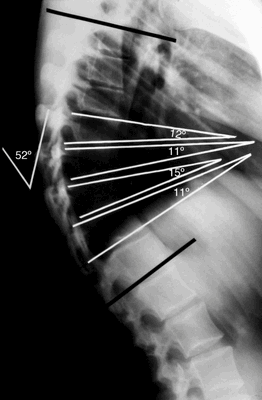

Кифоз Шейермана, также известный как болезнь Шейермана, ювенильный кифоз, или юношеская дискогенная болезнь - это гиперкифоз, при котором происходит клиновидная деформация трех и более соседних позвонков на ≥ 5 градусов.

Позвоночник взрослого человека имеет естественную S-образную форму. Шейный и поясничный отделы выгнуты вперед, эти изгибы называются лордозами. Грудной и крестцовый отделы выгнуты назад, эти изгибы называются кифозами. По данным Общества исследования сколиоза (Scoliosis Research Society), в норме кифотический угол в грудном отделе позвоночника составляет 20-40 градусов. Если величина кифотической дуги оказывается больше или меньше указанного значения, то в этом случае говорят о деформации позвоночника.

Друзья, совсем скоро состоится семинар «Сколиоз: виды, причины, лечение». Узнать подробнее…

При болезни Шейермана происходит структурная деформация тел позвонков и позвоночника в целом. При этом заболевании кифотический угол в грудном отделе составляет около 45-75 градусов. Кроме того, происходит клиновидная деформация трех и более соседних позвонков на 5 и более градусов. Клиновидные тела позвонков определяют природу гиперкифоза, который наблюдается при болезни Шейермана. Гиперкифоз может быть скомпенсирован поясничным или шейным гиперлордозом.

Рентгенограмма в боковой проекции

Согласно Sorenson, кифоз Шейермана характеризуется следующими критериями:

- Три или более соседних позвонков имеют клиновидную деформацию ≥ 5 градусов.

- Отсутствуют врожденные патологии позвоночника, а также его инфекционные заболевания и травмы.

Для оценки кифоза Шейермана необходимы тщательно собранный анамнез, физикальное обследование и рентгенограммы в боковой и передне-задней проекциях. Боковые рентгенограммы требуются при диагностике. Диагностическими критериями являются:

- Грубый гиперкифоз более чем 40 градусов.

- Передняя клиновидная деформация тела позвонка на 5 градусов или более (в трех или более соседних позвонках).

- Упражнения будут эффективны при условии, что в грудном отделе позвоночника еще не развита соответствующая жесткость и когда сагиттальная дуга еще не слишком высока (угол Кобба - от 44 до 55 градусов).